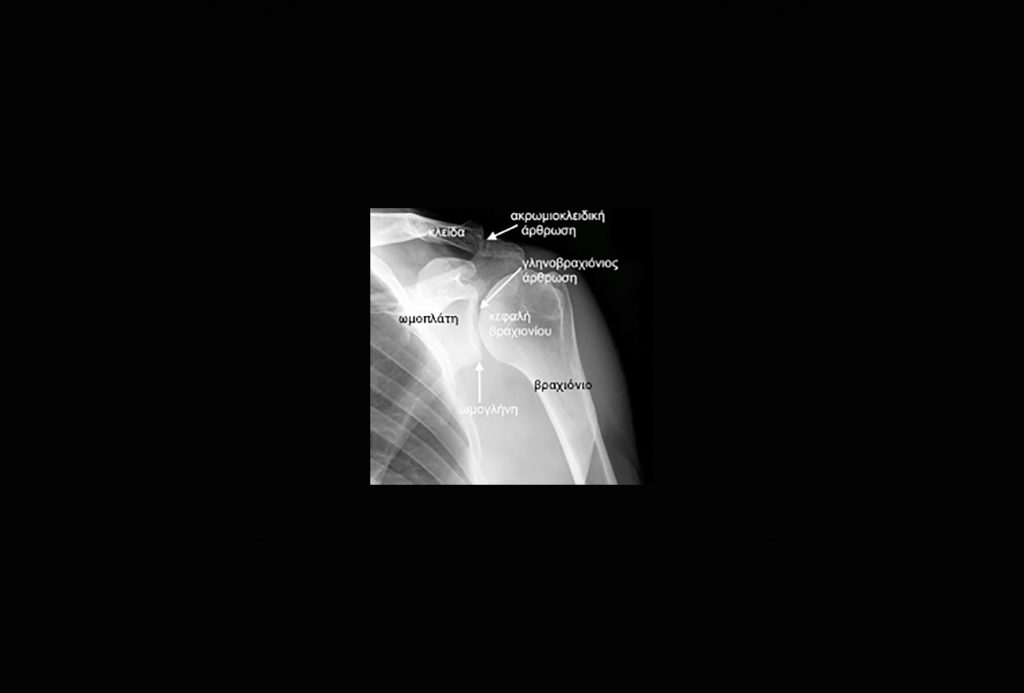

Πρόκειται για πάθηση της άρθρωσης του ώμου. Ο ώμος αποτελείται από τρία οστά, την κλείδα, την ωμοπλάτη και το βραχιόνιο οστό.

Ωμογλήνη είναι η αρθρική επιφάνεια της ωμοπλάτης, η επιφάνεια δηλαδή όπου “γλιστρά” η κεφαλή του βραχιονίου. Γύρω από αυτή βρίσκεται προσκολλημένος ο επιχείλιος χόνδρος (labrum), ο οποίος αυξάνει το εμβαδόν της ωμογλήνης και βαθαίνει ελαφρώς την υπόκοιλη επιφάνειά της, προσφέροντας αύξηση της σταθερότητας στην άρθρωση.